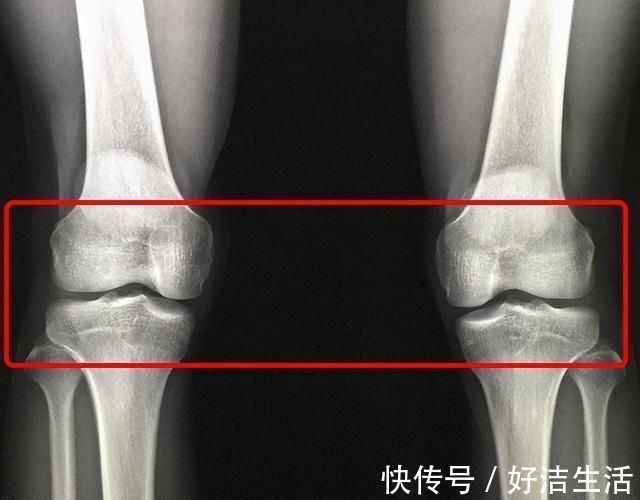

这次趁着自己体检的机会,妈妈悄悄地带孩子到儿科门诊检查。医生说:从遗传学来看,张放应该长到165 cm以上,但一查骨龄,他的骨骺线已基本闭合,最多还能长2-3 cm。这样的结果让妈妈不能接受,希望医生多想办法,但医生却表示无能为力。在排号等待时,刚好看到张放的同学也来体检,医生说:尽管这名同学和张放的情况相似,但他的骨骺线没有完全闭合,身高还有一定的上升空间。见此情景,妈妈更加后悔没早做检查,以致于错失良机。